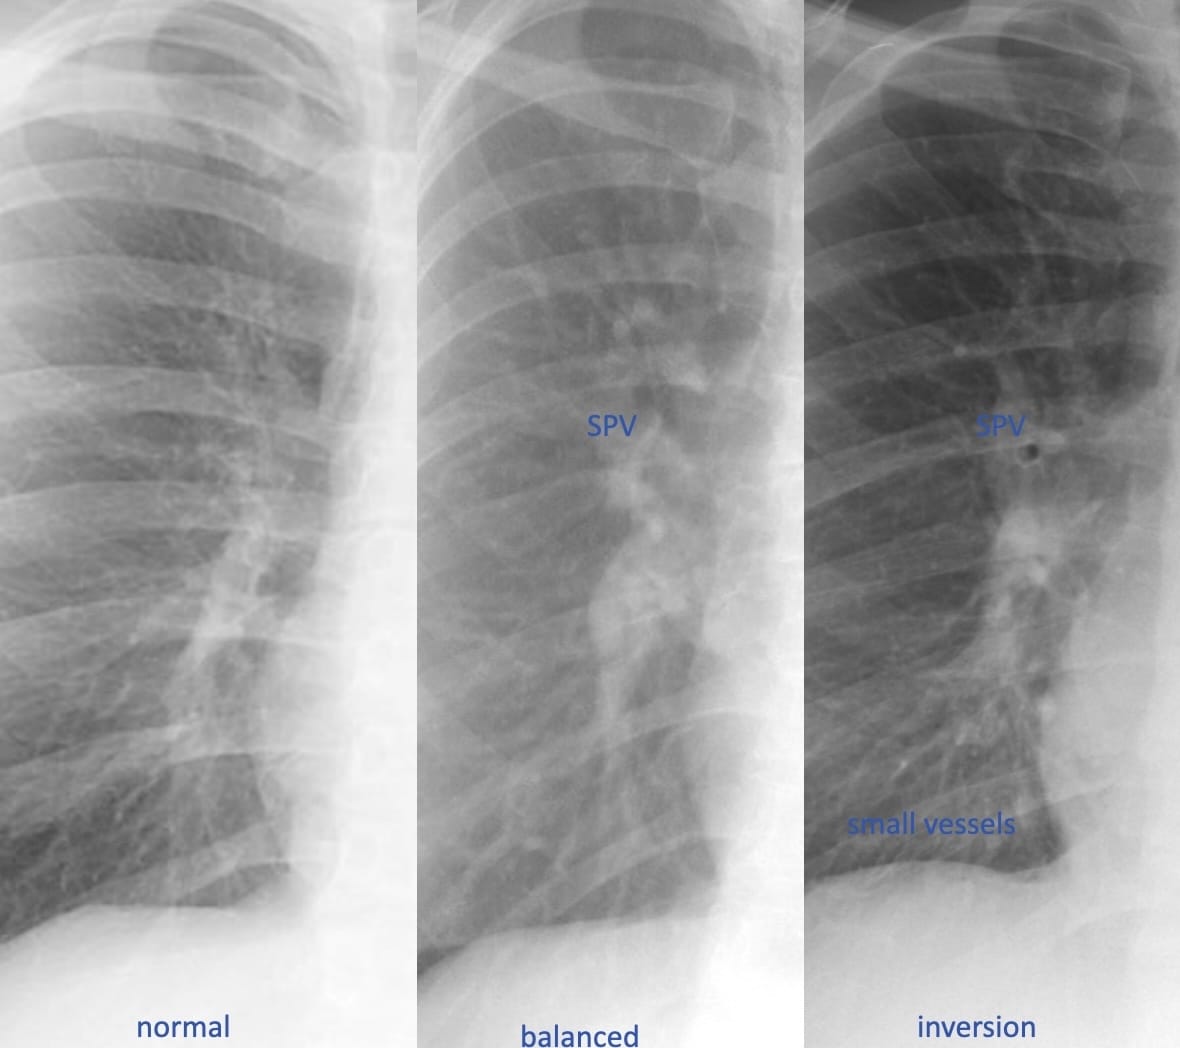

The distribution of pulmonary blood flow.

In the physiologic state, reflective of cranial-caudal hydrostatic pressure, the vessels—arteries and veins—in the lower lungs are slightly more distended than those in the upper lungs.

When pulmonary blood flow and volume is increased, as in a left-to-right shunt or hypervolemia, the vessels are distended, and equal in caliber from top to bottom.

In chronic—not acute—pulmonary venous hypertension, the upper zone vessels are more distended. This occurs because of pathologic changes—intimal hypertrophy and hyperplasia—that develop predominantly in these vessels over years. The resultant increase in regional vascular resistance results in the redistribution of blood flow.

Hydrostatic Lung Edema and Thoracic Vessels

The distribution of pulmonary blood flow.